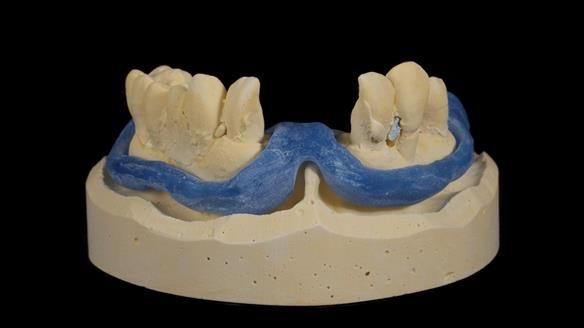

We provided her with an immediate upper denture (Mk 1), followed by a definitive metal-based upper denture (Mk 2). A lower removable partial denture was discussed, to be made only if needed once the upper treatment was complete. However, at review, this wasn’t necessary — Adnana had excellent neuromuscular control and function, even with a shortened dental arch (SDA).

Rowan, Sam Hesketh and Chris Hesketh provided the stunning technical work. I am very lucky to have them.

- Definitive denture (Mk 2), metal-based and custom-designed for her face